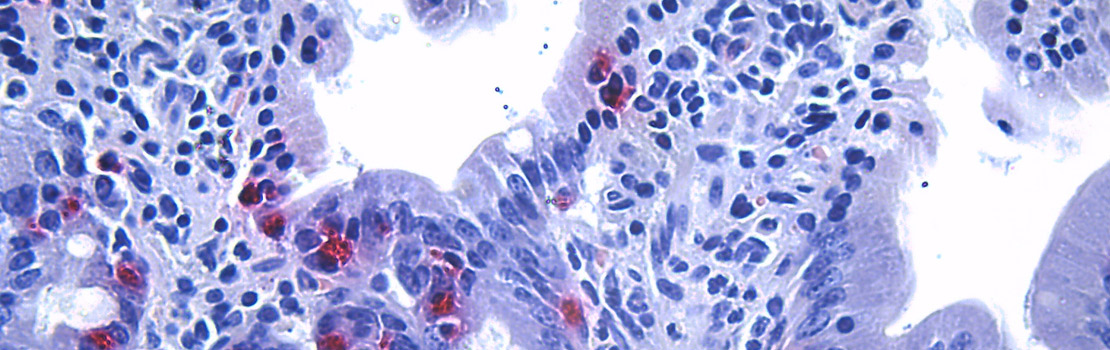

内脏微生物含有不同的微生物群落 通过改变消费模式猫类微生物P28和P35Bidobctium,Lactobcillus并美加法拉即可食用碳水化合物和蛋白质并食用对比之下 猫喂高蛋白P55克隆人 鲁米诺科库斯并Faecalibacterium.细菌食用粘结素 胶质素组成胃肠道粘结层微信防病原体P55食品消费限制了大肠中消化耐碳水合物的供应,因此这些细菌偏向于食用阻素